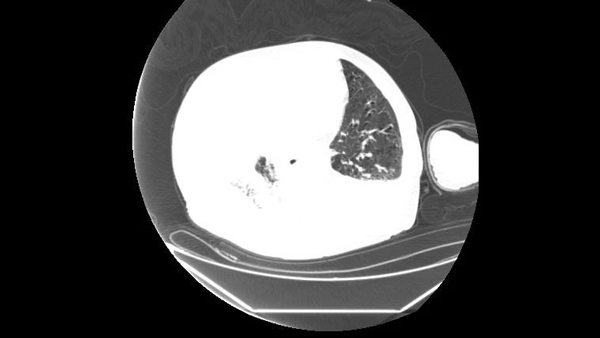

据了解,该患者年逾百岁,因严重呼吸系统疾病,气道内形成大量痰栓,导致呼吸困难、气道严重受阻,血氧饱和度急剧下降,生命危在旦夕。在此危急时刻,重症监护室迅速集结我院呼吸与危重症医学科团队,共同商讨救治方案。

手术过程中,医师们凭借娴熟的操作技巧,谨慎而精确地将支气管镜插入患者气道。在支气管镜的直视下,凭借对气道解剖结构的深入理解和精湛的手术技巧,准确锁定痰栓位置。结合适度的负压吸引,将痰栓逐一、彻底地吸出。同时,配合肺泡灌洗治疗,有效清除了气道内的分泌物和炎症介质,恢复了气道的通畅性。患者的呼吸状况得到了显著改善,血氧饱和度迅速回升至正常范围,生命体征逐渐稳定。